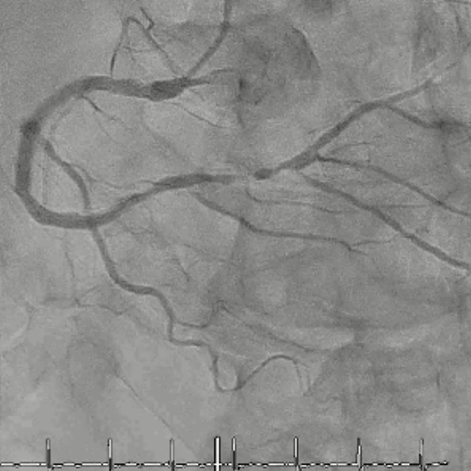

CAG

RCA distalの高度石灰化狭窄病変

OAS low3回 造影上の切削区間の確認

末梢病変であるがOASはGlide Assistで容易にdeliveryできた